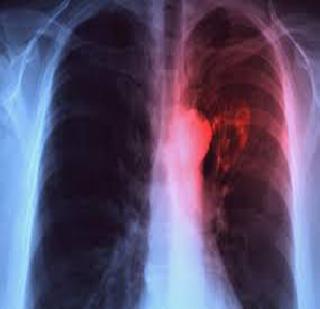

टीबीने भारतालाच नाही तर जगाला ग्रासले असून, टीबी रुग्णांची संख्या झपाट्याने वाढत आहे. टीबी हा संसर्गजन्य आजार असल्याने प्राथमिक अवस्थेतच त्याच्यावर उपचार होणे आवश्यक आहे.

मुंबई : टीबीने भारतालाच नाही तर जगाला ग्रासले असून, टीबी रुग्णांची संख्या झपाट्याने वाढत आहे. टीबी हा संसर्गजन्य आजार असल्याने प्राथमिक अवस्थेतच त्याच्यावर उपचार होणे आवश्यक आहे. टीबीला प्रतिबंध करण्यासाठी नव्या लसीची निर्मिती होण्याची आवश्यकता या क्षेत्रातील तज्ज्ञ व्यक्तींनी व्यक्त केली आहे.

टीबीच्या विषाणूंच्या गुणसूत्रांमध्ये बदल होत आहेत. या बदलांमुळे टीबी वाढत आहे. विषाणूंच्या गुणसूत्रात होणाऱ्या बदलांमुळे टीबीसाठी नवीन लसीची आवश्यकता आहे. पण प्रत्यक्षात अशाप्रकारे नवीन लस येईल असे चिन्ह नाही. संशोधन सुरू असेल, पण परिणामकारक लस यायला अजूनही काही काळ जावा लागणार असल्याचे मत श्वसनविकारतज्ज्ञ डॉ. झरीर उदवाडिया यांनी सांगितले.